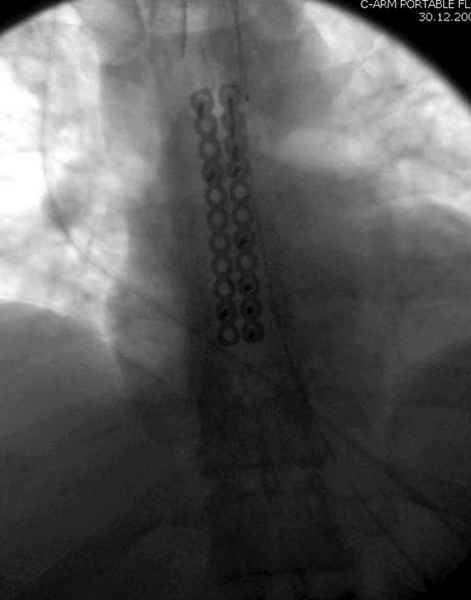

"классический" остеосинтез проволокой, иногда подкладываю шайбы, чтобы не прорезалась

Юра, интересно, насколько такой остеосинтез контролирует степень репозиции, а то у меня имеются снимки девочки 11 лет, направленной ко мне на консультацию из одной из республик бывшего союза.

После торакальной операции, по-видимому, сильно натянули проволоку, и в результате получился захлест отломков в друг друга.

А простые посттравматические ложные суставы грудины приходилось оперировать с ограничителем сверла и с фиксацией 2.4 мм пластинами с угловой стабильностью.